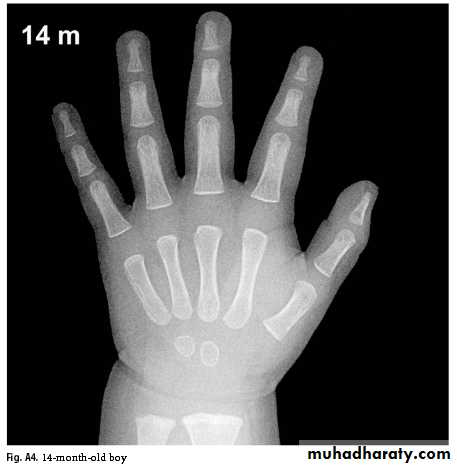

Bone Age

Greulich & Pyle: Radiographic Atlas of Skeletal Development of the Hand and Wrist, This method involves a complex comparison of all the bones in the hand and wrist against reference radiographs of different ages.Delay of 2 years or more in bone age is significant.